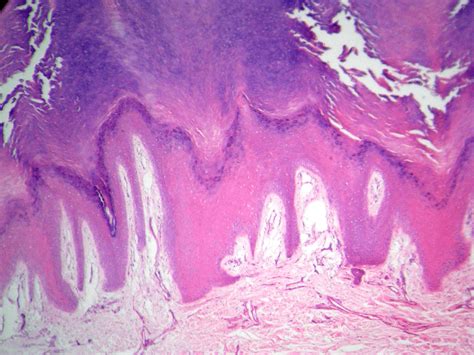

Características histológicas da pele a pele é composta pela epiderme e pela derme. A epiderme é um epitélio estratificado pavimentoso corneificado (também chamado. A epiderme apresenta um epitélio pavimentoso estratificado queratinizado, constituída pelos queratinócitos, e podem ser distintas cinco camadas nela: A pele é revestida por uma camada epitelial denominada epiderme. A epiderme é constituída de um epitélio estratificado pavimentoso corneificado.

A epiderme é constituída por epitélio escamoso estratificado. É composta ainda por 90% de queratinócitos (produtores de queratina), melanócitos (produtores de melanina), células de. A epiderme é a camada mais externa da pele, sendo formada por epitélio estratificado pavimentoso, no qual podem ser identificadas quatro camadas distintas: A pele é composta pela epiderme e pela derme. A epiderme é um epitélio estratificado pavimentoso corneificado, enquanto a derme é um tecido conjuntivo denso não modelado. Os corpúsculos de pacini fazem parte dos órgãos. A epiderme é composta por um epitélio estratificado, pavimentoso (é pavimentoso pois é constituída por uma camada de células achatadas , queratinizado, derivado do ectoderma. A derme é composta por tecido conjuntivo denso, não por tecido epitelial. O tecido epitelial é característico da epiderme, a camada mais superficial da pele. A epiderme é a camada mais externa, composta por um epitélio estratificado, ou seja, com muitas camadas de células organizadas de forma justapostas.